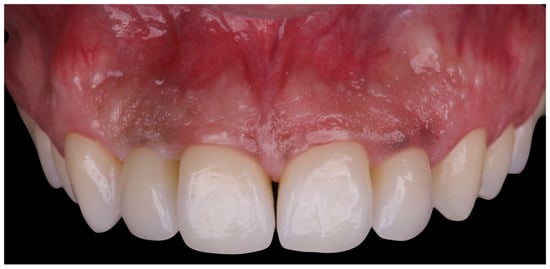

The patient was subsequently enrolled in a structured periodontal and prosthetic maintenance programme, with follow-up evaluations scheduled at four-month intervals to monitor periodontal health, occlusal stability, and the integrity of the prosthetic components (Figure 18, Figure 19 and Figure 20).

Figure 18. Final intraoral image.

Figure 19. Intraoral image at four-year follow-up.

At the four-year follow-up, clinical evaluation demonstrated stable soft and hard tissues, with no biological or mechanical complications observed throughout the entire follow-up period.

At the four-year follow-up, the clinical situation remained stable and asymptomatic. Periodontal evaluation revealed probing depths within physiological limits, a low plaque index (7%), and minimal bleeding on probing (8%), all consistent with a healthy periodontal environment. Radiographic assessment confirmed the maintenance of alveolar bone levels without signs of resorption. The patient’s reduction in tobacco use and adherence to four-month maintenance therapy intervals likely played a pivotal role in sustaining these outcomes. The four-year follow-up also confirmed the clinical stability of the treatment, both occlusally and periodontally, with a significant improvement in clinical indices and complete patient satisfaction. Masticatory function remained effective, the deep bite was corrected, and the interincisal diastema was successfully closed, resulting in a harmonious and stable aesthetic outcome. The final decision to fabricate individual crowns was justified by the favourable tissue response and the occlusal stability achieved.